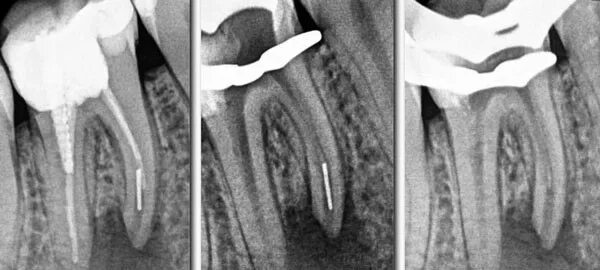

Пломбирование перфорации